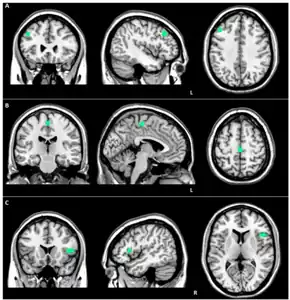

![]() | |

| Brain MRI of a female of 65 years with frontotemporal dementia. Cortical and white matter atrophy of the frontal lobes is clear in all images. | |